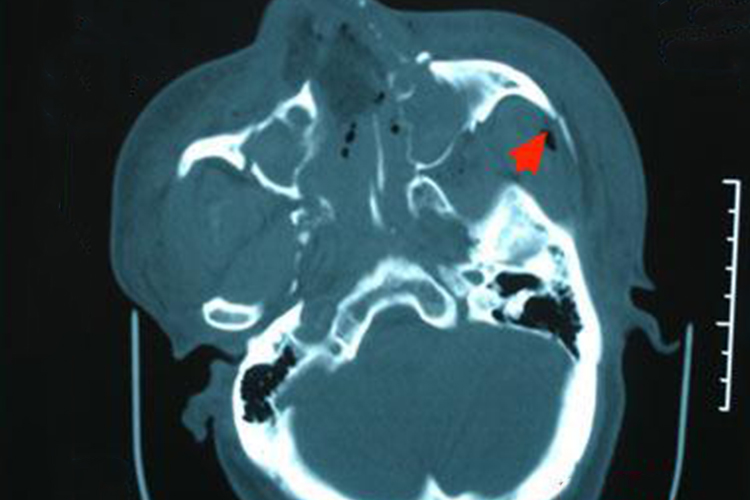

颧骨骨折:颧骨骨折多发生内陷,移位面部塌陷。骨折移位后,因眼球移位、外展肌和下斜肌受累致眼球运动受限而出现复视。颧骨眶壁有闭合性骨折时,眶周皮下眼睑和结膜下可有出血性瘀斑。如损伤面神经额支,则发生眼睑闭合不全。颧骨骨折时常可合并上颌窦外侧壁损伤,窦内出血常从鼻腔流出。

上颌骨骨折:可发生上颌骨向内上方或外上方的嵌顿性错位,局部塌陷,咬合错乱,常同时伴有翼突骨折。眶周还可发生水肿,皮下瘀血呈青紫或蓝紫色,呈典型的“眼镜”症状。如发现鼻腔及外耳道出血,呈淡红色血水,应考虑发生脑脊液鼻漏或耳漏。